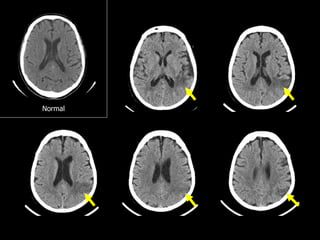

Microangiopathic change

Normal

Microangiopathic change  Youmay encounter the term ā€œmicroangiopathic changeā€ in reports and wonder what it is  Microangiopathic change refers to age-related white matter ischemia due to microvessel disease  Very commonly seen in the elderly  Its clinical significance is still not known Microangiopathic change Normal